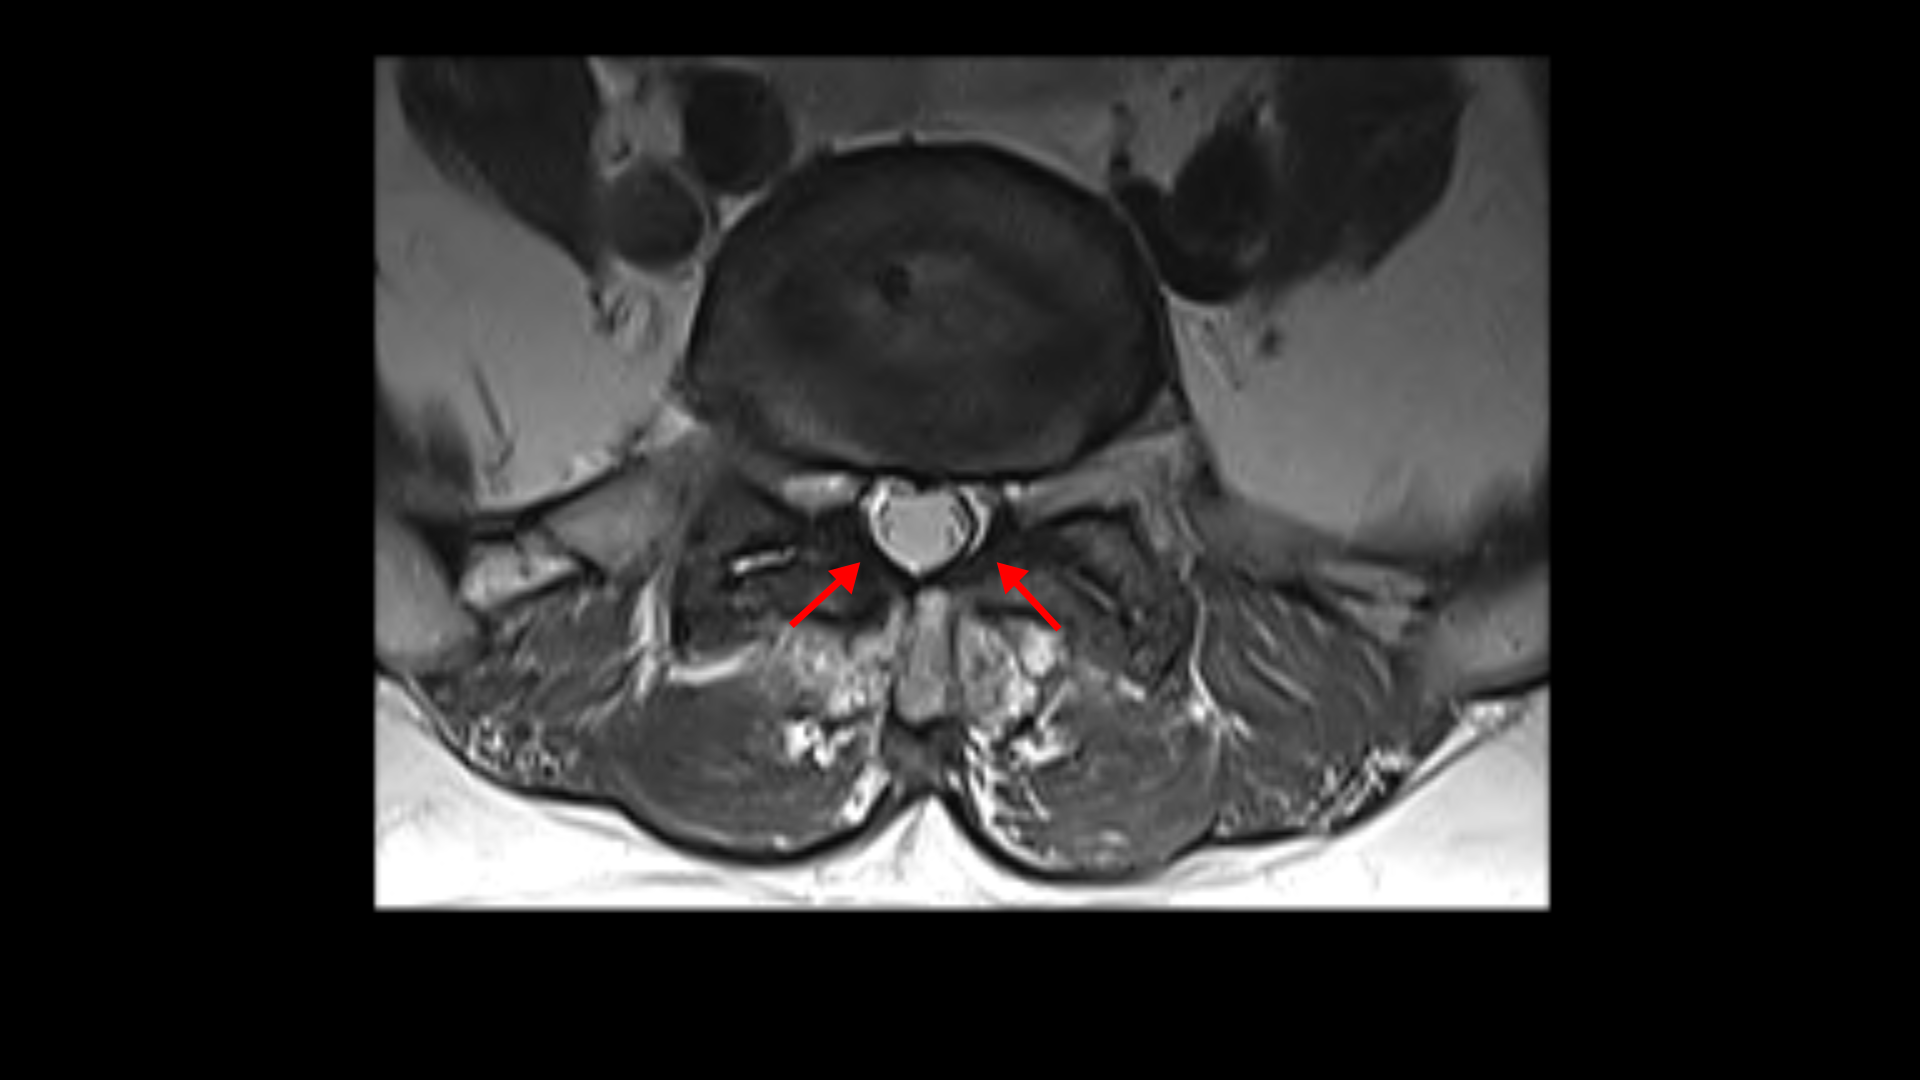

우선 이 환자분의 X-ray를 보면 5번 1번에 전방전위증으로 인한 불안정성이 있습니다. 척추가 불안정하므로 전방전위로 뼈가 밀려 나간 정도가 MRI에 보이는 것보다 X-ray 굴곡상태에서 보는 게 훨씬 더 심해 보입니다. 또 척추 여러 마디에 퇴행성 병변이 보입니다.

먼저 5번 1번에 척추관 내의 황색인대의 골화 현상이 보이고

후관절의 퇴행도 심해 보입니다.